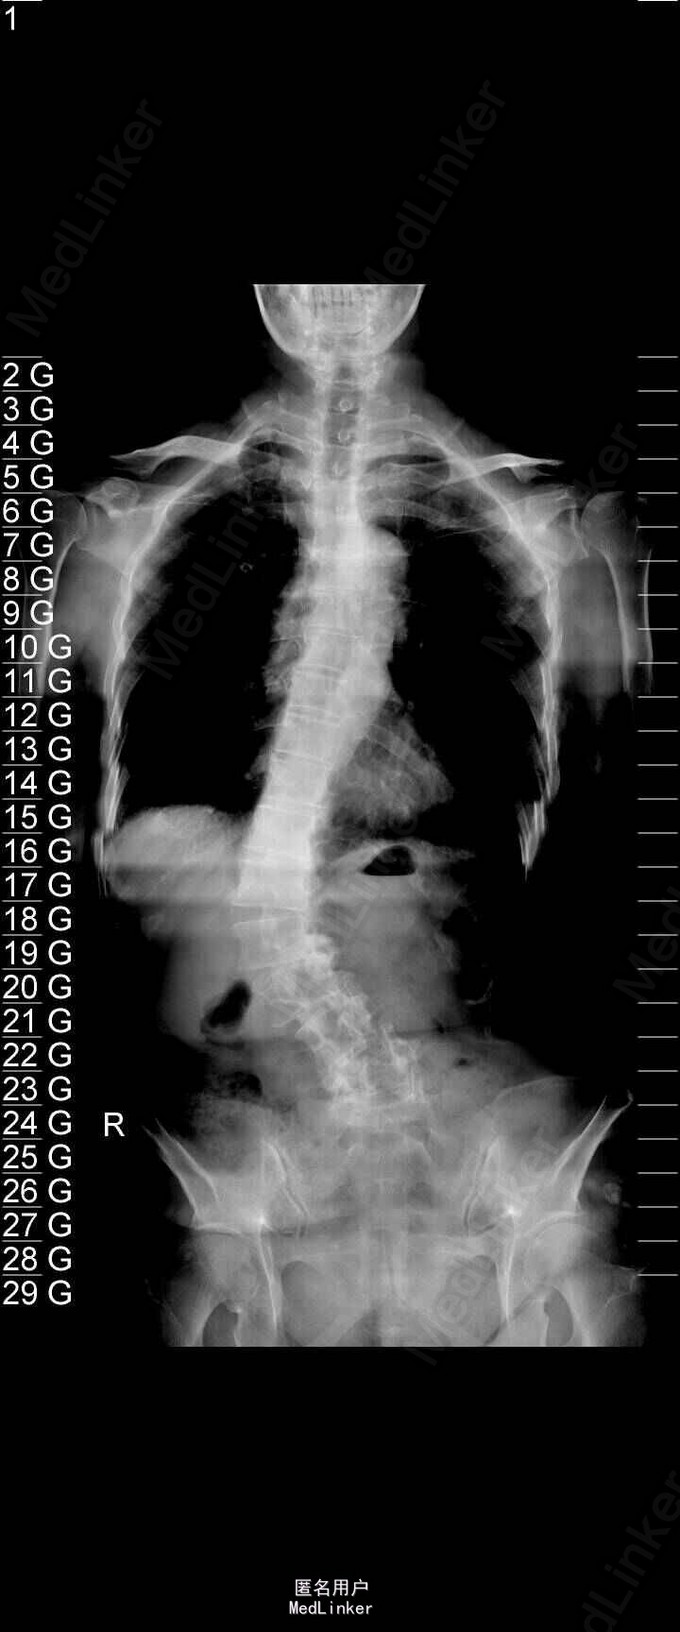

主诉:右下肢麻木伴驼背11年余 病史:患者女性,64岁,11年前无明显诱因出现右下肢疼痛,休息后好转。未予重视,后出现右下肢麻木感,逐渐小狐仙右臀部坚硬,驼背,伴跛行。常感双腿酸胀,腰部疼痛。自行步行距离小于200米,即会发生右下肢僵硬,麻木疼痛。X线检查示腰椎侧弯

查体:脊柱侧弯,上肢无麻木,疼痛感觉异常,腰部右侧疼痛,右下肢及右臀部疼痛,麻木感。双侧肌力及肌张力可,膝腱反射(+),踝反射(+),病理征(—),直腿抬高试验。右侧40度,左侧55度。 辅助检查:腰椎x线片:腰椎侧弯,腰椎退行性改变,L5椎体略行前滑脱 脊柱全长:胸腰段呈S形,L5椎体向前滑脱,L3椎体略变扁,颈胸腰椎退行性改变 MRI:脊柱侧弯,L2-3,L3-L4,L4-L5,L5-S1椎间盘突出,相应节段椎管狭窄

诊断:腰椎侧弯,腰椎椎管狭窄 治疗:手术矫形:早期侧路减压融合,后期再行后路固定。